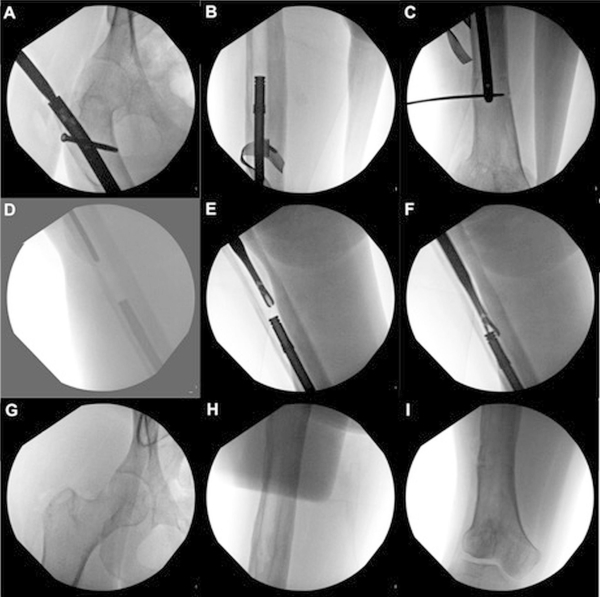

Disociación de un clavo alargador magnético intramedular femoral durante la extracción del implante de rutina